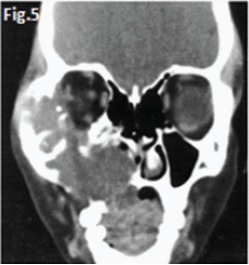

This 22 year old male patient (Figs.1 & 2) presented with a slow growing swelling in the left mandibular molar region. Figures 3, 4, 5 & 6 are images of three other patients with the same condition. Discuss the radiological features and what is your diagnosis?

Fig 1 & 2: the large lesion of left mandible shows a honeycomb-like distribution of calcifications. The borders are corticated. The tumour has displaced the mandibular molar tooth. A histological diagnosis of calcifying epithelial odontogenic tumour (Pindborg Tumour) was made. Fig.3 shows a Pindborg tumour distal to left second premolar associated with displacement of the first molar tooth. Fig.4 shows a similar tumour with mixed lucency-opacity between right premolar and molar teeth. Figs 5 & 6 show coronal and axial CT views of a large Pindborg tumour affecting the right maxilla. Note the marked expansion and cortical destruction. Calcifying epithelial odontogenic tumour is a rare benign neoplasm, accounting for less than 1% of all odontogenic tumours. The average age at diagnosis is 40 years; however, the tumour can occur at any age. It occurs equally in males and females. Approximately two thirds of cases are reported to occur in the mandible. Most cases occur in the premolar-molar area and are commonly associated with an unerupted tooth. The tumour is a painless, slowly enlarging mass. Histologically the tumour has a very characteristic appearance. Sheets of polyhedral cells with well-defined eosinophilic cytoplasm and hyperchromatic nuclei are featured. Amyloid and ringlike calcification may also be present. The tumour may be irregular or, in some cases, the cystic lesions may be well defined and corticated, whereas others appear ill defined. Small unilocular lesions may have a completely radiolucent centre (Fig.3). Others may have variable amounts of small flecks of calcifications scattered throughout. Larger lesions have a multilocular or honeycomb appearance. The tumour can displace and often prevent the eruption of teeth. Radiologically the tumour may be very similar to the calcifying odontogenic cyst, adenomatoid odontogenic tumour and ameloblastic fibro-odontoma.